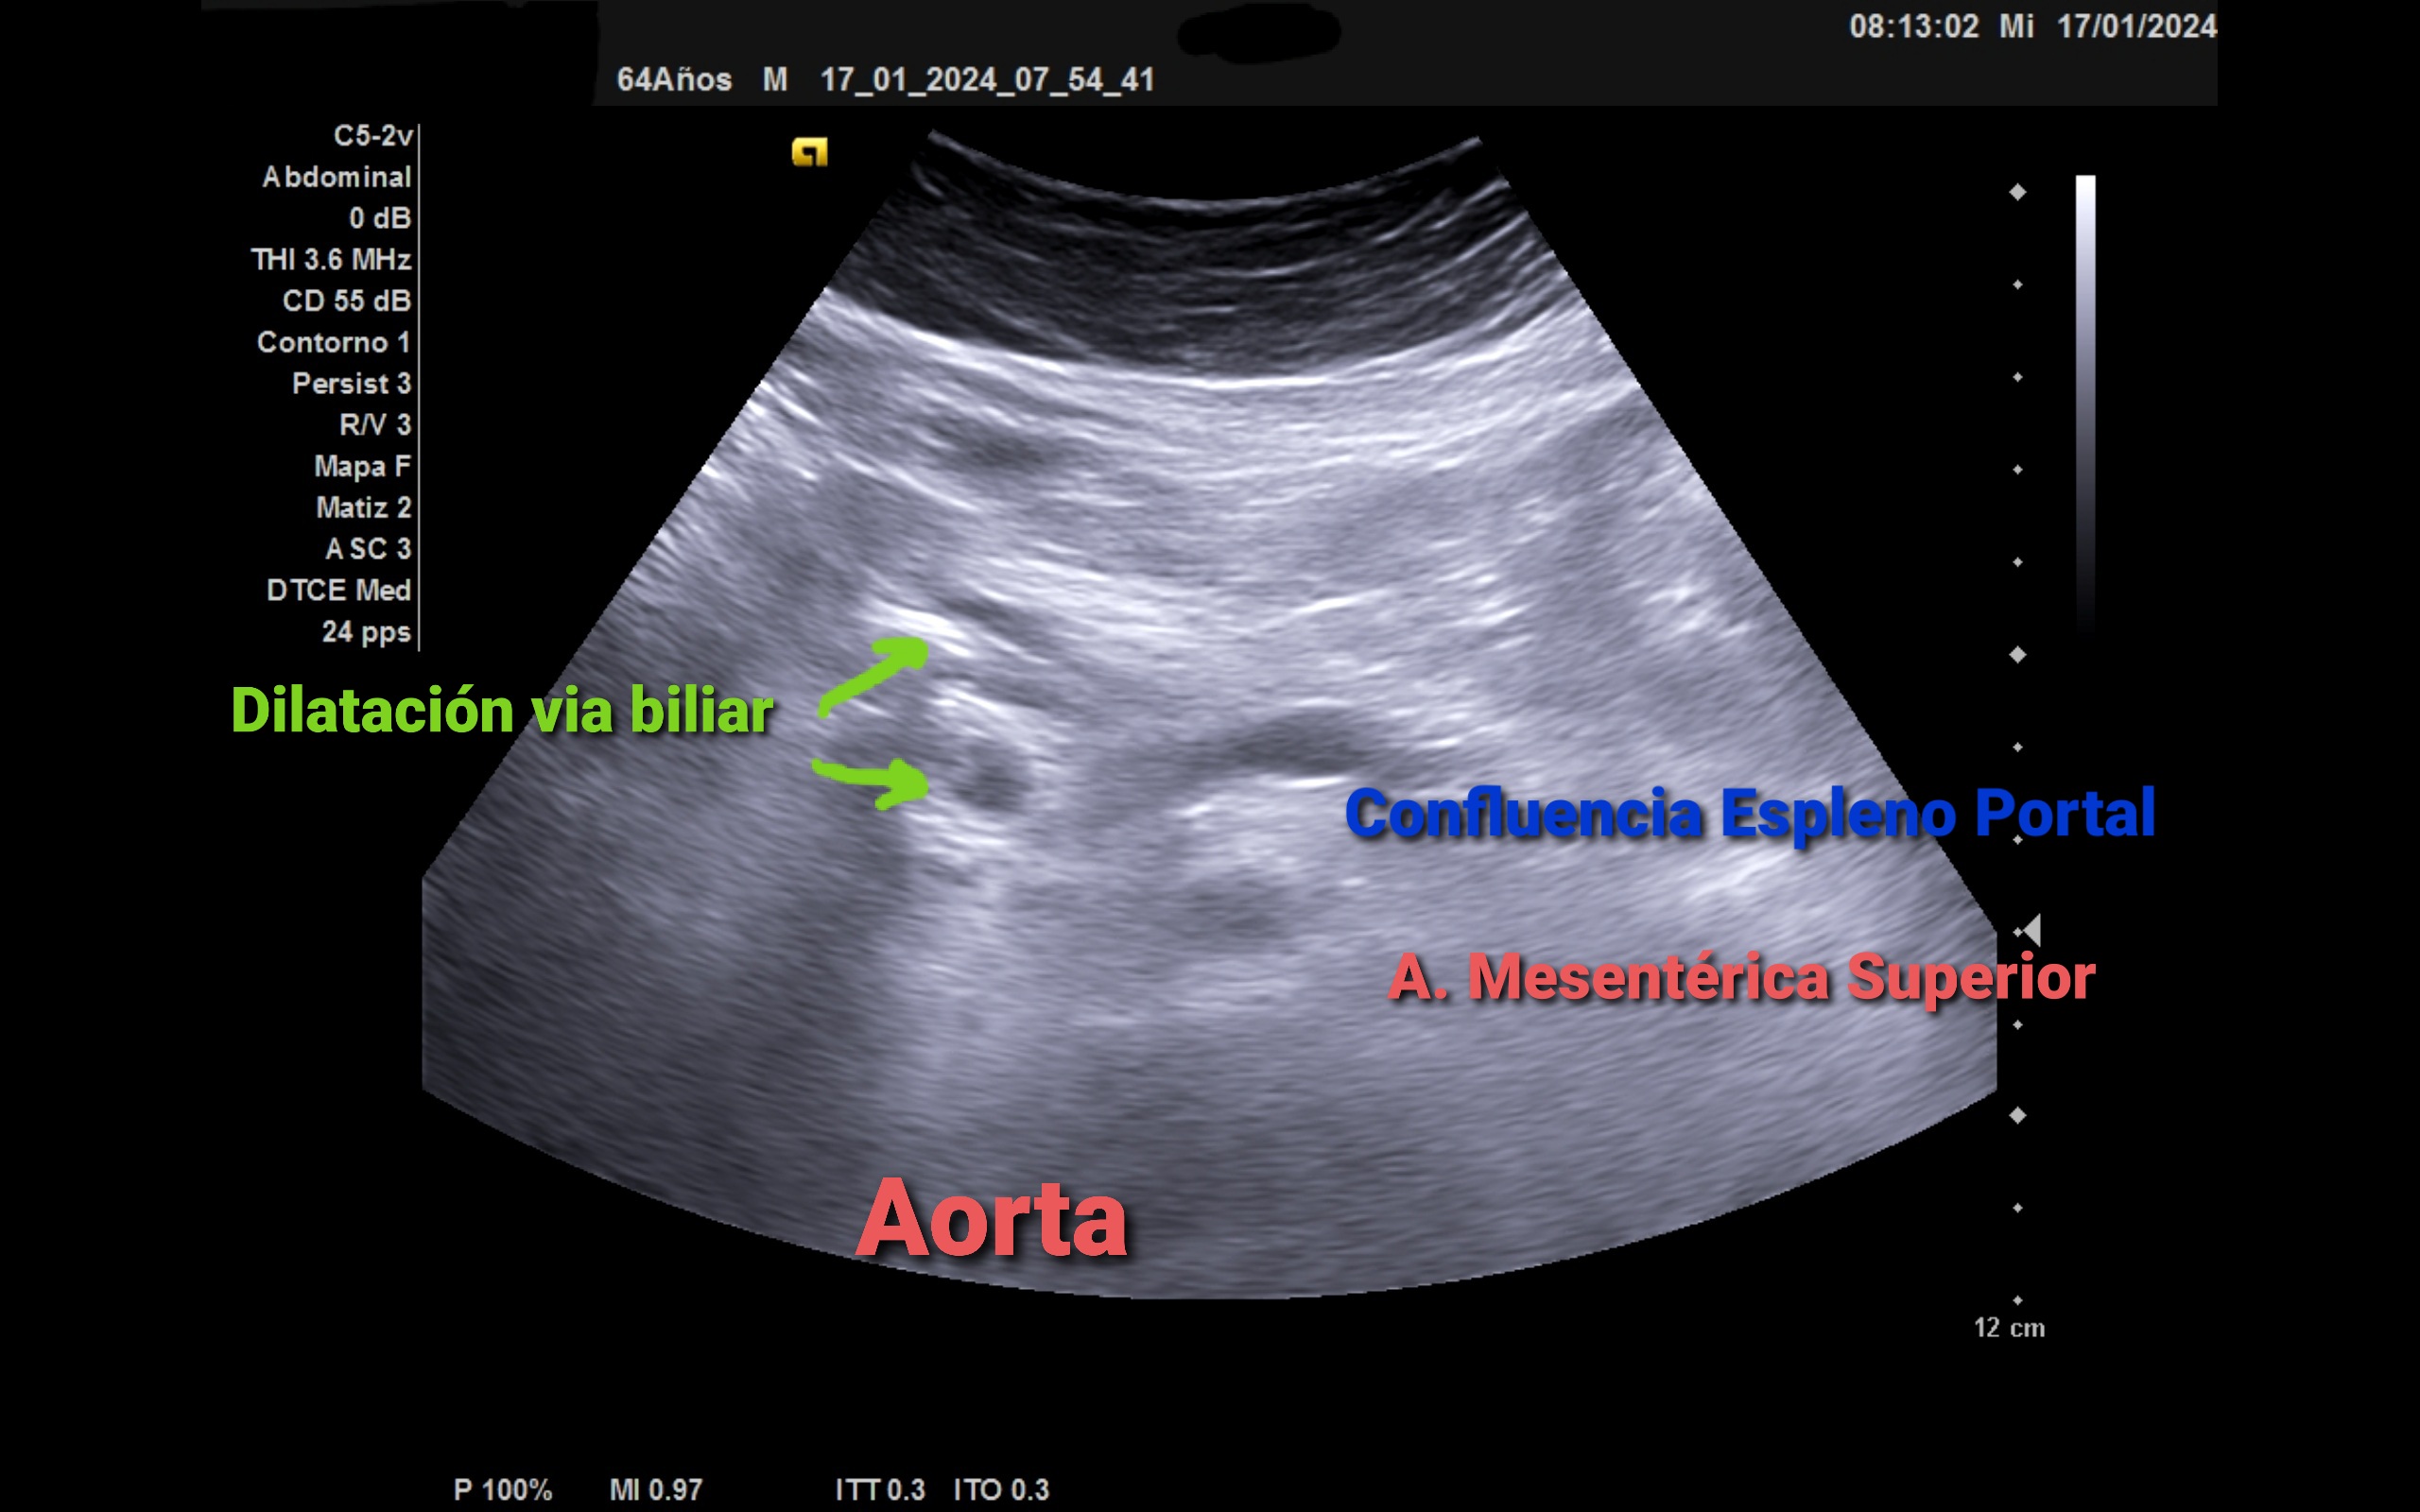

Ecografía clínica: Ventana subóptima. Parenquima hepático homogéneo con atenuación posterior, ángulo lóbulo hepático derecho redondeado, no aprecio claramente vesic biliar por imagen hiperecogénica con sombra. Pancreas visible, imagen anecogénica de 15 mm circular que no capta. Imagen tubular anecogénica: coledoco 13 mm. No aprecio alteración renal. Vejiga de la orina no replecionada. Ilíaca bilateral de 13,7 mm. Aorta de calibre normal.

Ictericia con Colelitiasis Múltiple con Dilatación de la via biliar con Stop ecográfico a nivel de pancreas.

La detección de la dilatación de la via biliar dilatada en paciente con hábito enólico nos hace sospechar la etiología maligna. Debe valorarse tanto parénquima hepático como pancreático, bazo y retroperitoneo.